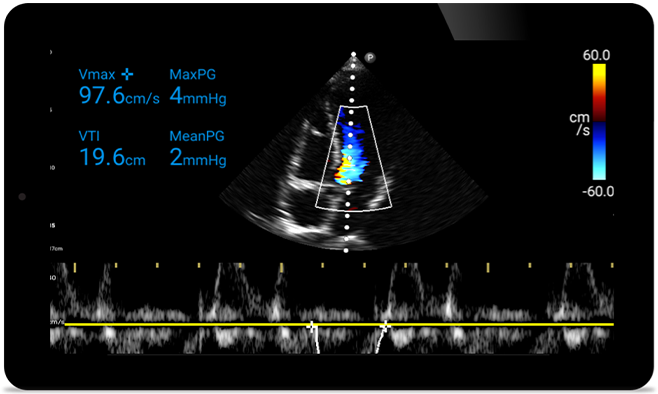

• 2D, Color Doppler, M-mode, advanced, XRES and multivariate harmonic imaging.

• High-resolution imaging for abdominal and cardiac applications: cardiac, OB/GYN, lung, abdomen and FAST imaging preset optimizations.

Padstatic case example image

See more when it counts

From revealing the subtle details of an image to uncovering enriched tissue definition from multiple angles, Lumify can help you make real-time decisions with more confidence from assessment through recovery.